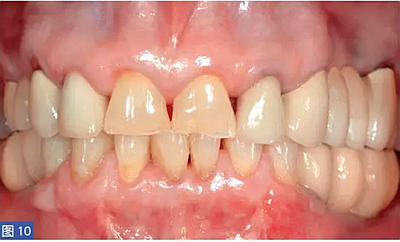

圖10:病例1. 術(shù)后12個(gè)月,臨時(shí)修復(fù)體。